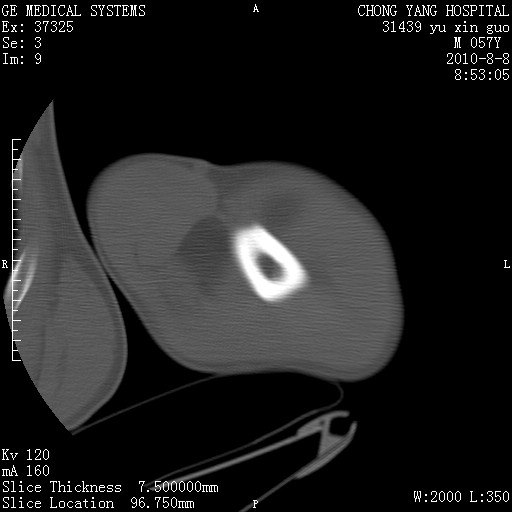

标题: CT28267:M57Y 上臂包块8年余。 [打印本页]

标题: CT28267:M57Y 上臂包块8年余。

典型脂肪瘤改变

上臂软组织内脂肪瘤。

包膜光滑、完整的脂肪密度肿块,支持脂肪瘤。

脂肪瘤。有ct值?